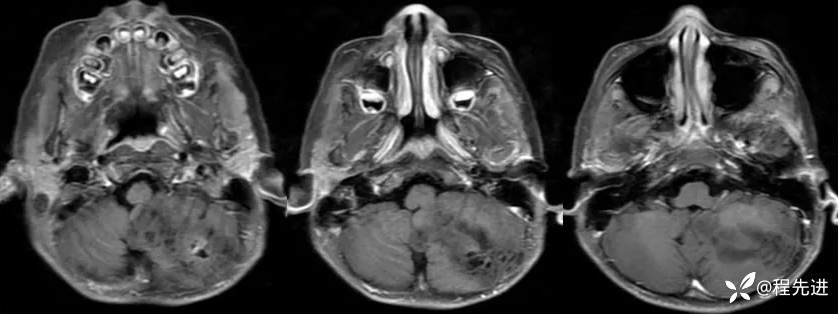

【患者信息】:男,6岁

【主诉】:查体发现左侧小脑半球占位3个月

【现病史及既往史】:患者3个月前因鼻塞至外院就诊,行头颅CT检查偶然发现颅内占位

【检查】